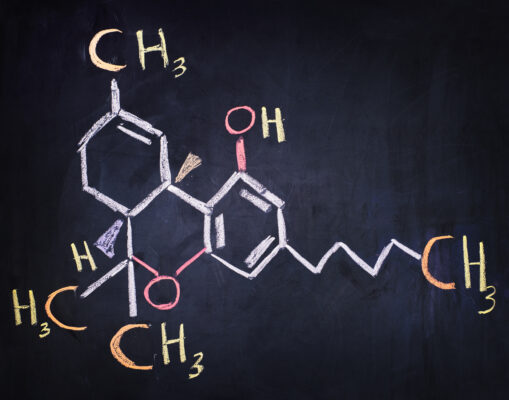

Understanding THC and Your Body’s Pain Response

THC works by interacting with your body’s endocannabinoid system (ECS), a complex network of receptors, enzymes, and naturally produced cannabinoids that help regulate various bodily functions, including pain perception. The ECS contains two primary receptors: CB1 receptors, predominantly found in the brain and nervous system, and CB2 receptors, located mainly in immune cells and peripheral tissues.

When THC enters your system, it binds primarily to CB1 receptors, potentially altering pain signals before they reach your brain. This interaction may reduce the intensity of pain sensations and improve your overall comfort levels. Additionally, THC’s interaction with CB2 receptors may help reduce inflammation, addressing one of the root causes of many painful conditions.

Research suggests that THC’s pain-relieving properties work through multiple pathways. It may reduce the release of pain-signalling neurotransmitters, decrease inflammation in affected tissues, and potentially alter your emotional response to pain. This multi-faceted approach makes THC particularly interesting for managing complex pain conditions that don’t respond well to conventional treatments.